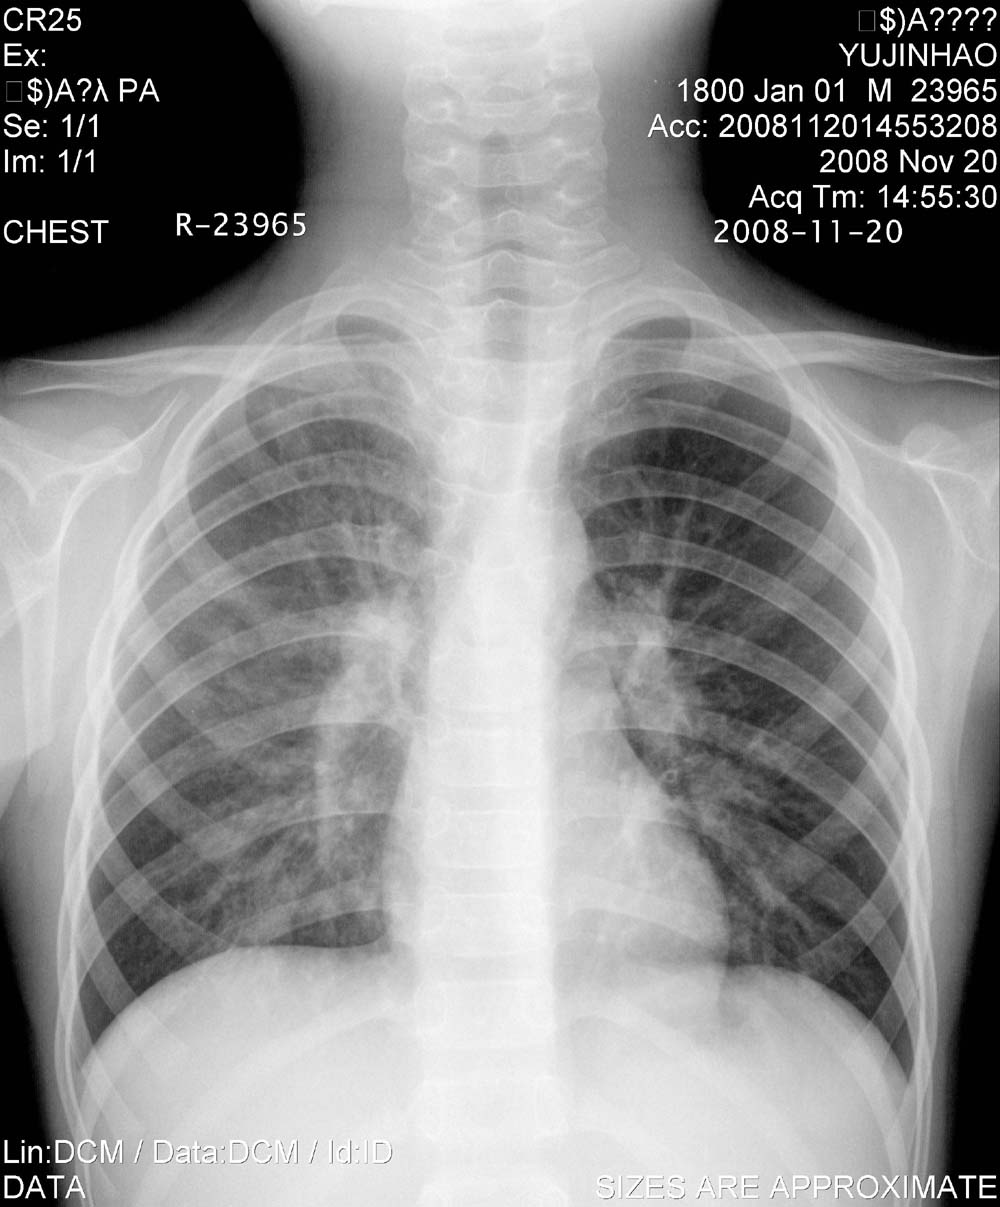

标题: PED1647:男,10岁,发热咳嗽5天就诊,请会诊。

男,10岁,发热咳嗽5天就诊,38-39度,血沉90    wbc12000,ttp(—)治疗6天无好转,复查胸片肺似有播散。

锁骨上下区,片状阴影,边界尚清,中等密度,治疗后胸片,右肺透光度下降,肺纹理增多增粗,象结核,参考。

右肺短期内有游走改变,考虑过敏性肺炎。

原发性的肺结核之肺发灶有消散快且自消散的特点,本例前后两张片对比后片右肺门较前片有所增大,考虑淋巴结肿大可能.所以不除外原发三联征及肺门淋巴结核转变.

右肺短期内有游走改变,考虑过敏性肺炎,建议查痰内噬酸粒细胞。

寄生虫类所致的过敏性肺炎可能性大,化验室查嗜酸性粒c及虫卵。